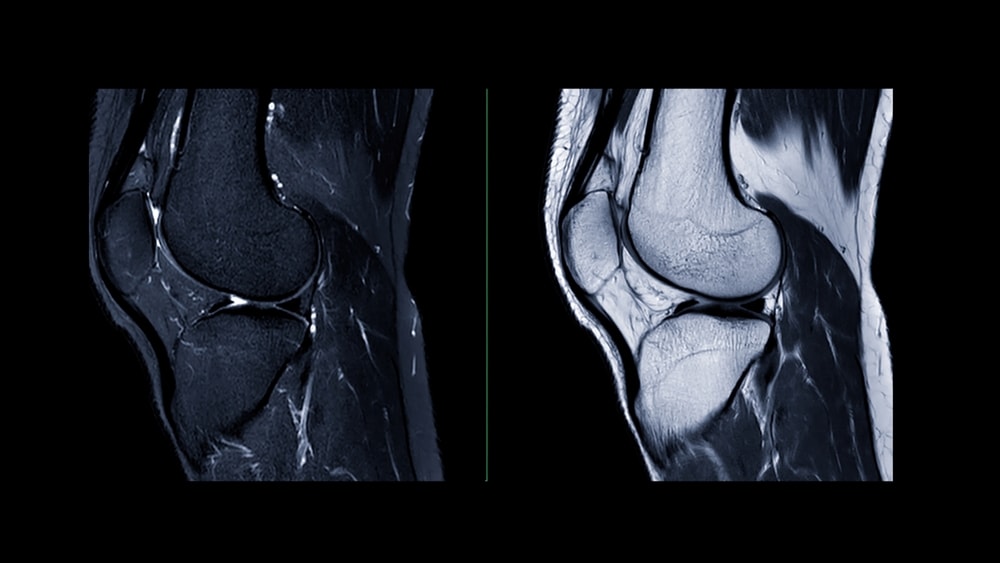

Risonanza magnetica: è l’esame di riferimento per visualizzare legamenti, menischi e cartilagine e per definire il quadro complessivo.